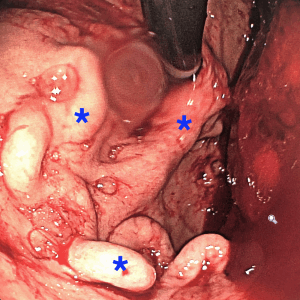

Existem diversas causas possíveis de sangramentos digestivos, como por exemplo, neoplasias, úlceras, varizes esôfago-gástricas, divertículos, aneurismas viscerais e angiodisplasias. Grande parte das hemorragias digestivas são auto-limitadas, ou seja, melhoram com medidas clínicas, entretanto, em algumas situações pode ser necessário um procedimento de embolização para controle do sangramento.

Um pequeno cateter é introduzido por meio desse furinho, de forma indolor, e então navega por dentro das artérias até chegar ao ponto onde esteja ocorrendo o sangramento.

Em seguida, o médico Radiologista Intervencionista provoca a oclusão dessas artérias (embolização), a fim de obstruir o seu fluxo sanguíneo e, consequentemente, o sangramento. Ao final do procedimento retiram-se os cateteres e é feito um curativo no local do furinho.